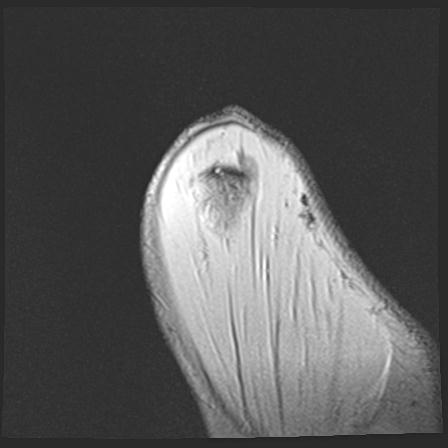

60058 3/9 11/4 右肩 2R+MRI 73歳男性 肩腱板損傷